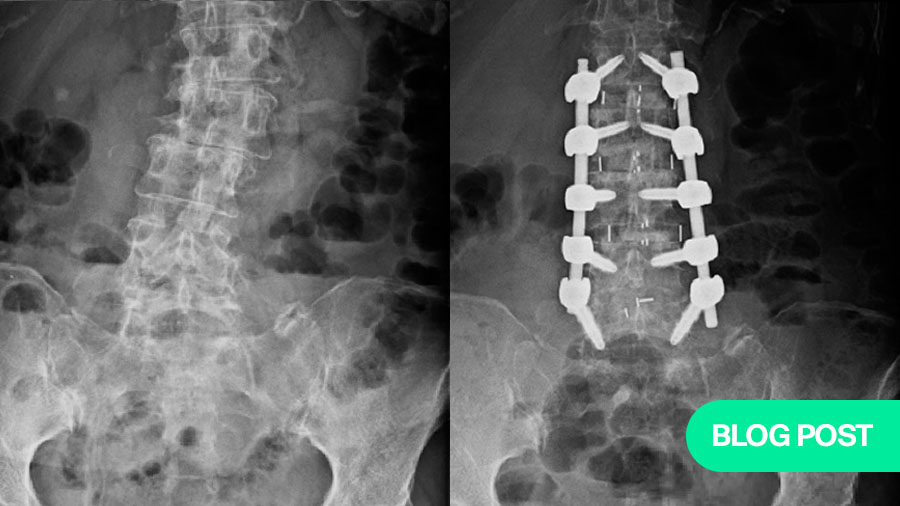

Coronal Cobb’s correction

It is well known that, degenerative lumbar deformities are often associated with coronal translation of the vertebral body and asymmetric disc space collapse. This malalignment is better suited for correction on the same plane as the deformity. This is one of the important advantages of the pre-psoas corridor as it helps to effectively correct the asymmetric disc space collapse, coronal obliquity, and lateral vertebral translation and improves the overall C7-CSVL balance.

Note the coronal imbalance in the patient. Fusion performed using the pre-psoas approach, showing the vertebral bodies almost horizontal with a good correction of the coronal Cobb’s angle.